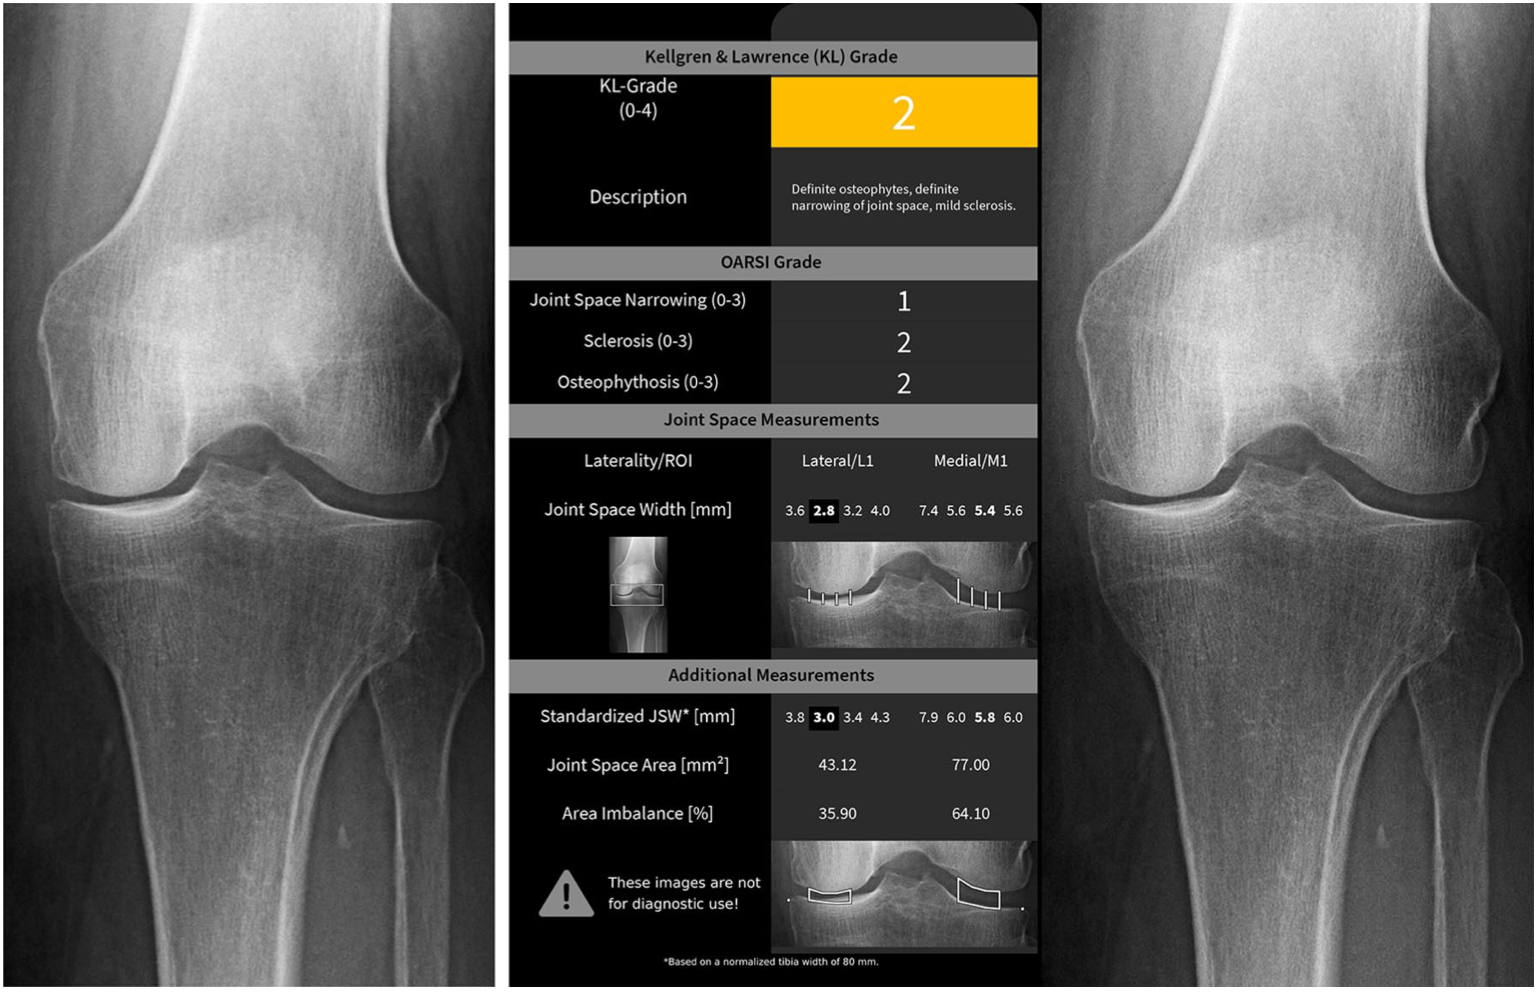

Age correlated with KellgrenLawrence score, but not OARSIScore. A Kl Score Radiology The original paper 1 graded oa at the. Grading of joint osteoarthritis by kellgren and lawrence uses plain radiograph to assess the extent of degenerative disease. These changes can by examined radiographically and quantified using the semiquantitative grading scale known as the. Different grading schemes are described for plain radiographs of the hip: Although many new and modified scores have. Kl Score Radiology.

From www.imagebiopsy.com

Automated Knee Osteoarthritis Assessment Increases Physicians Kl Score Radiology Grading of joint osteoarthritis by kellgren and lawrence uses plain radiograph to assess the extent of degenerative disease. The original paper 1 graded oa at the. Different grading schemes are described for plain radiographs of the hip: The kellgren and lawrence system is a common method of classifying the severity of osteoarthritis (oa) using five grades. Kl scores were based. Kl Score Radiology.